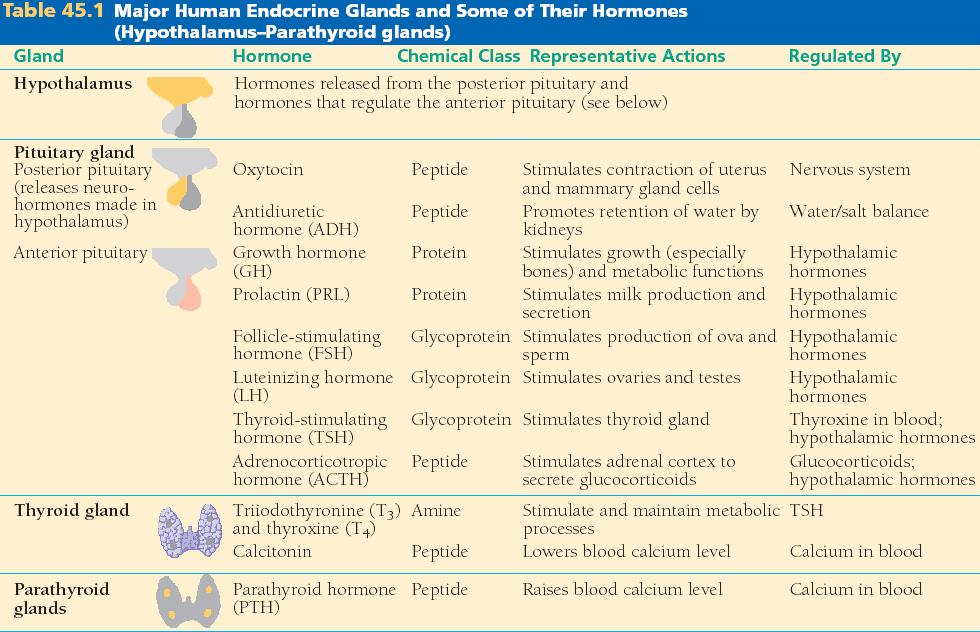

45_01aEndocGlandsHypo_T